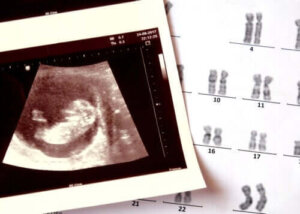

Anencefalie is een aangeboren ziekte die bestaat uit de afwezigheid van de ontwikkeling van sommige delen van het zenuwstelsel en de schedel van de baby.

Deze gezondheidstoestand is opgenomen onder de neurale buisdefecten, een groep aangeboren pathologieën die ook spina bifida omvat.

Veranderingen in de chromosomen (structuren die alle genen van de cellen bevatten) en enkele specifieke mutaties kunnen bijdragen aan het verschijnen ervan. Blootstelling aan bepaalde omgevingstoxines is ook onderzocht als een mogelijke determinant. De onderzoeksresultaten zijn op dit moment echter nog niet overtuigend.